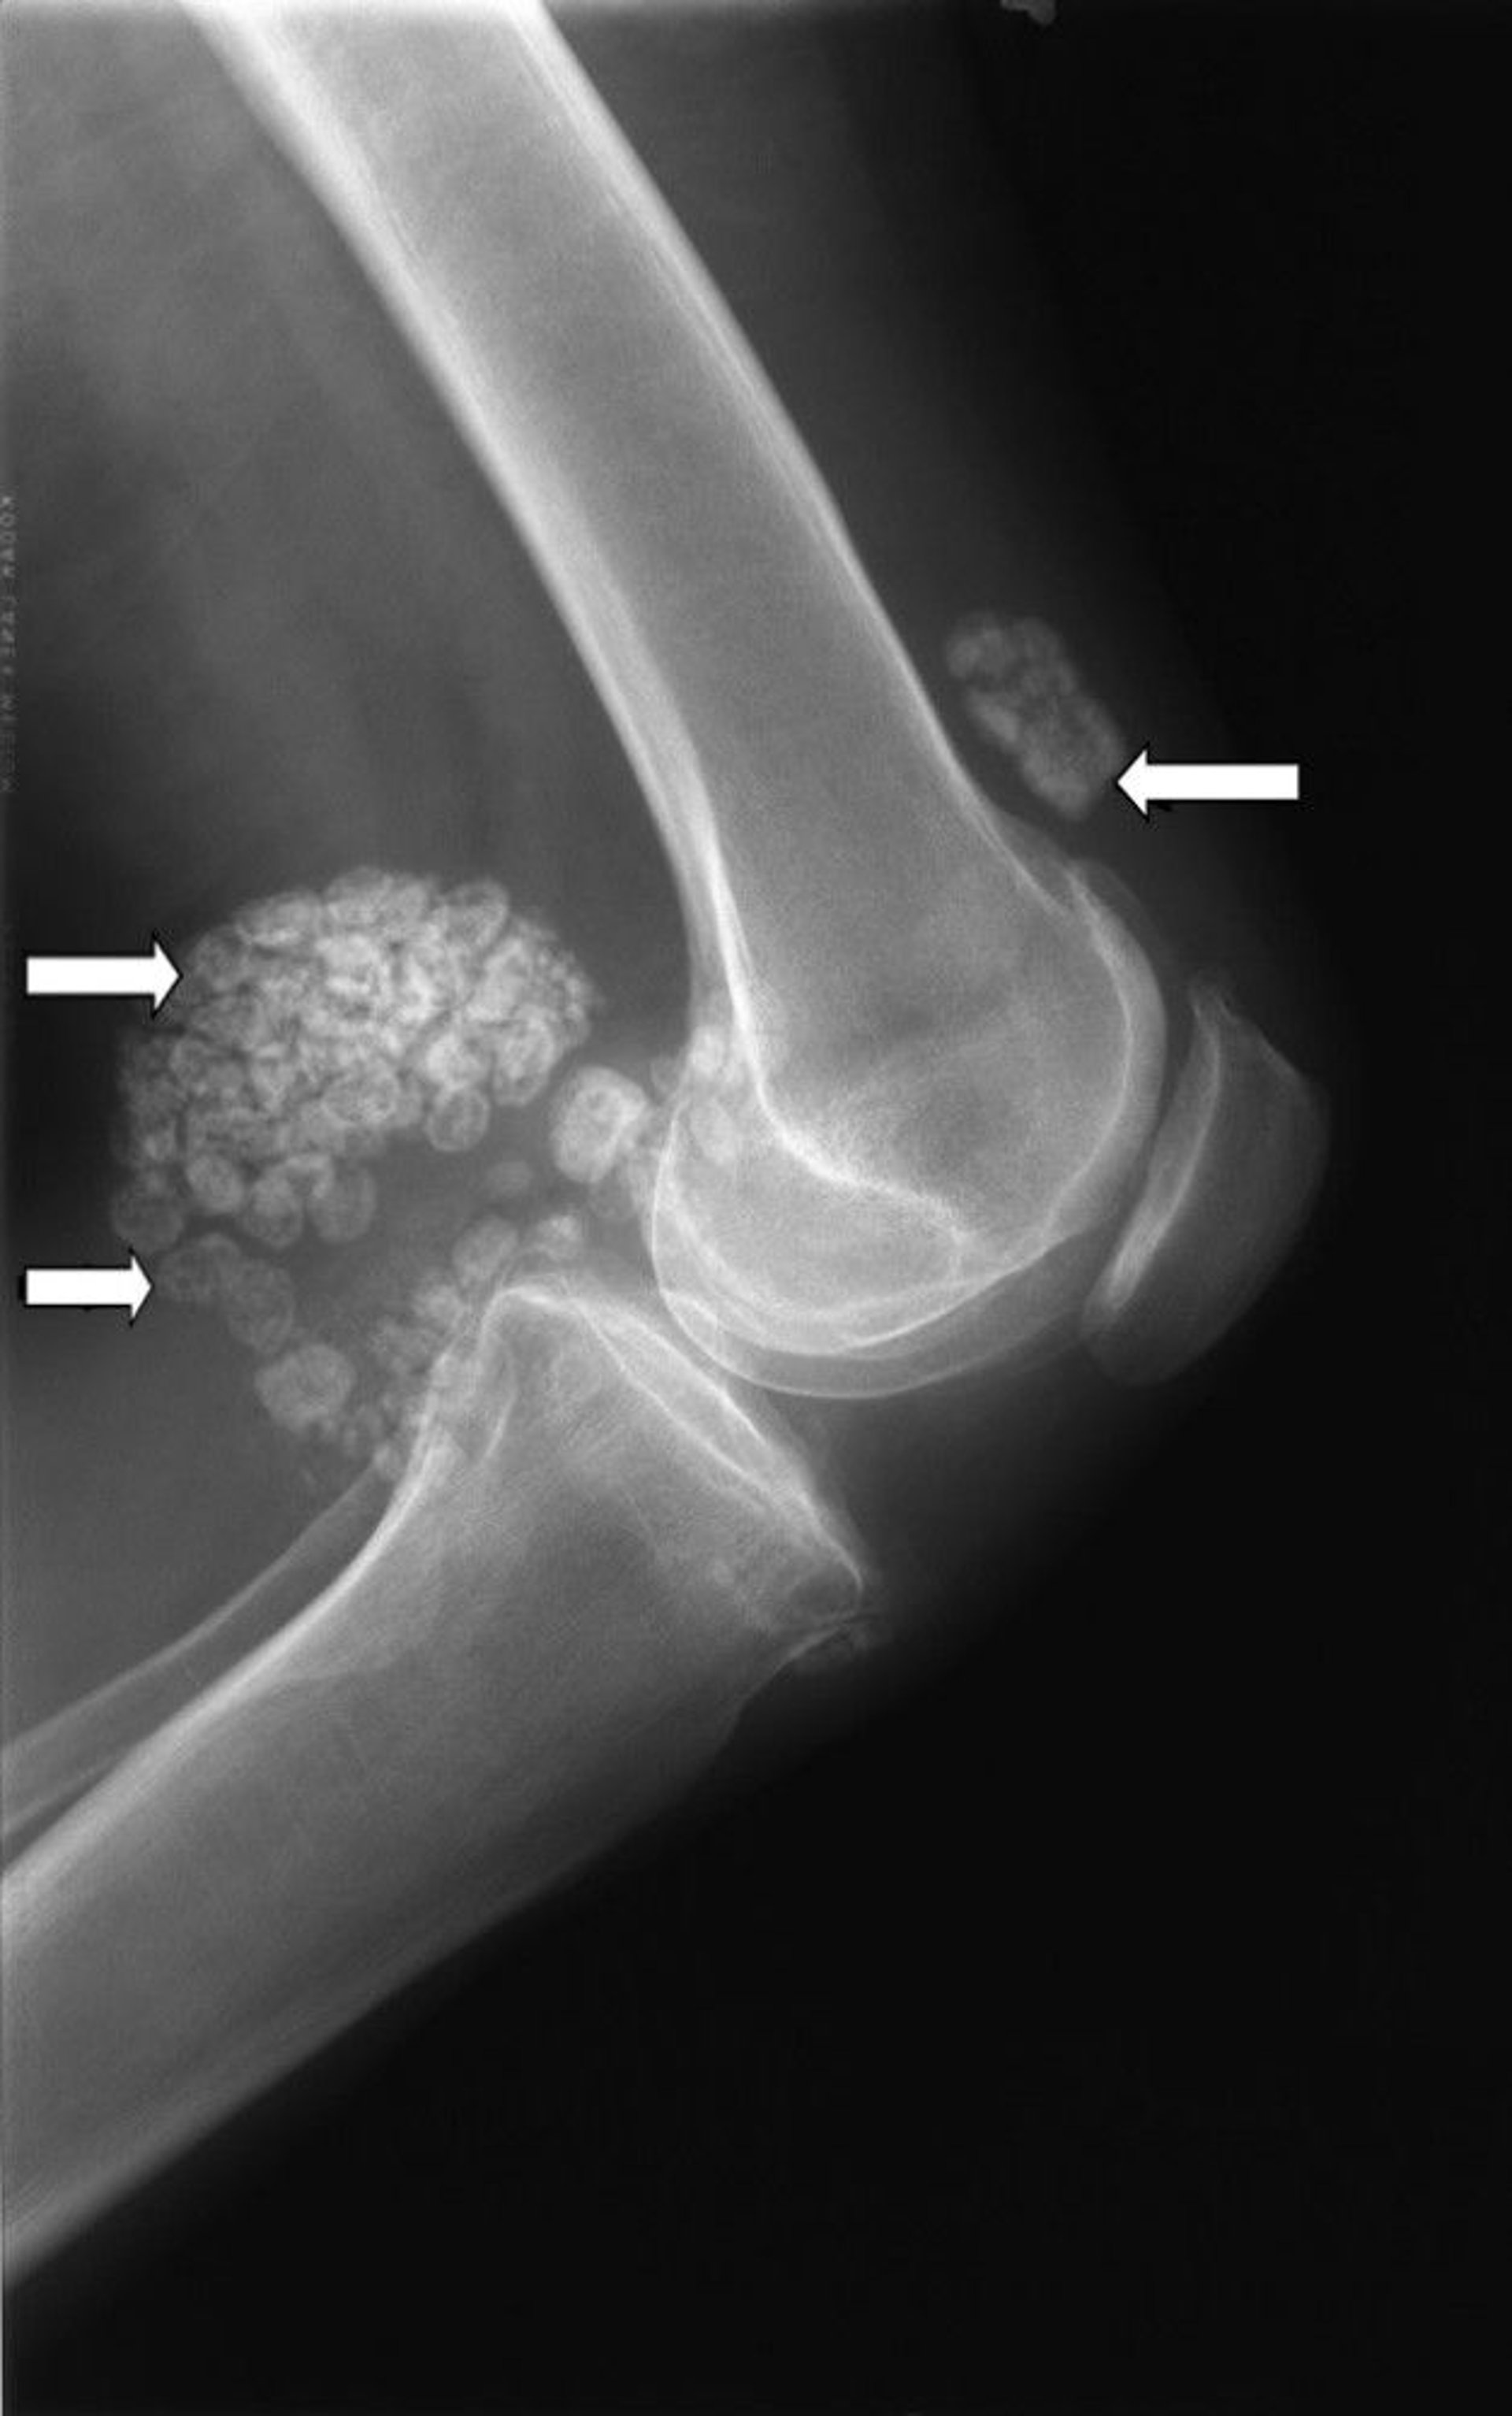

Pemeriksaan sinar-x pada lutut ini menunjukkan beberapa gumpalan tulang rawan (panah) yang dikenal sebagai kondromatosis sinovial.

Gambar milik Michael J. Joyce, MD, dan Hakan Ilaslan, MD.